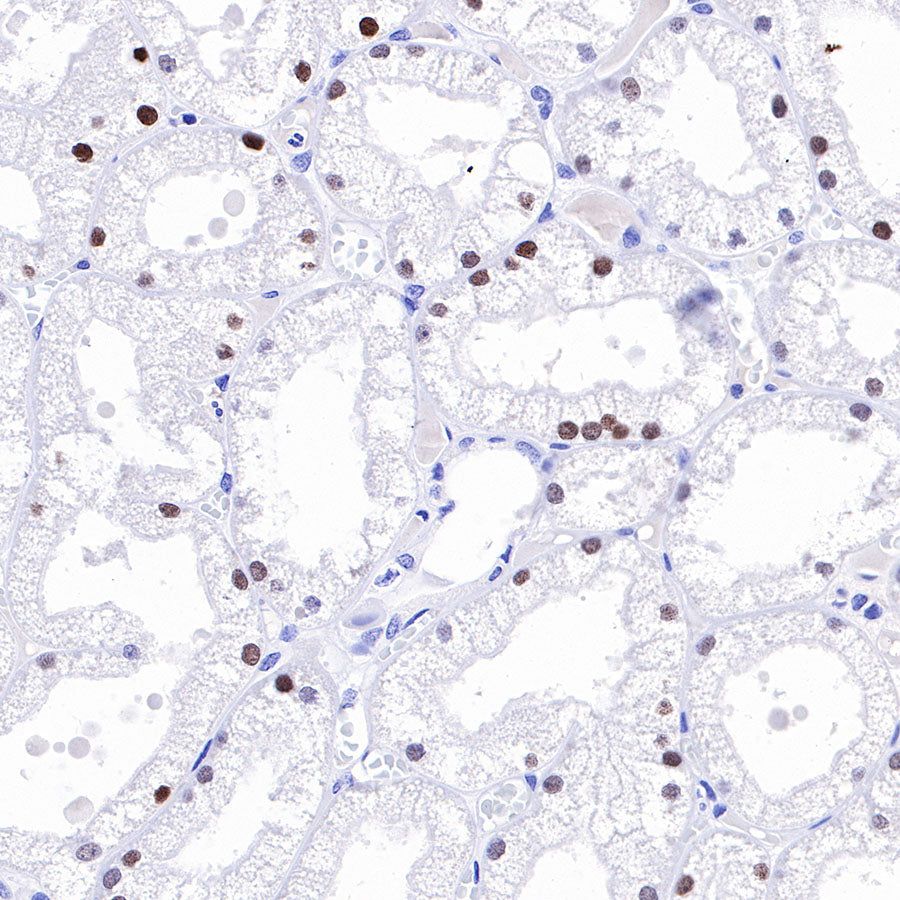

Immunohistochemistry

IHC shows positive staining in paraffin-embedded mouse liver. Anti-HNF4α antibody was used at 1/500 dilution, followed by a HRP Polymer for Mouse & Rabbit IgG (ready to use). Counterstained with hematoxylin. Heat mediated antigen retrieval with Tris/EDTA buffer pH9.0 was performed before commencing with IHC staining protocol.